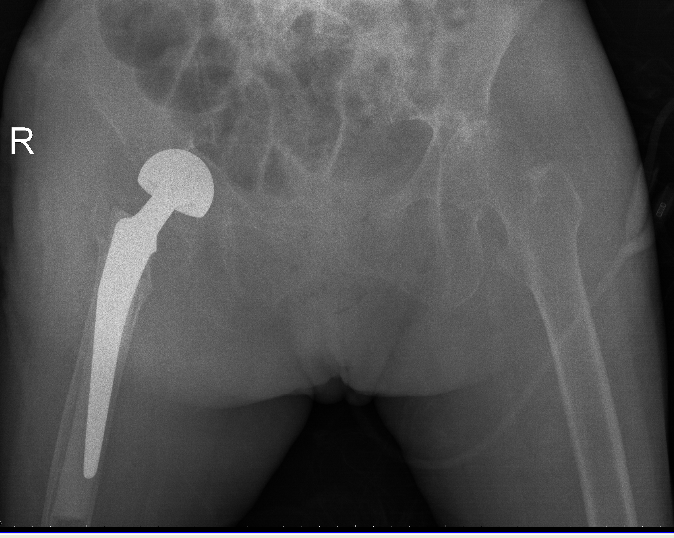

△骨科于15日、16日收治的另外兩位高齡患者

△術前

△術後